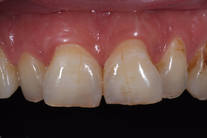

Missfärgade tänder 5

Kraftigt missfärgade tänder och fyllningsskarvar samt karies. Behandling: Generell blekning, 6 fasader och 4 kronor i överkäken samt 6 kronor i underkäken.